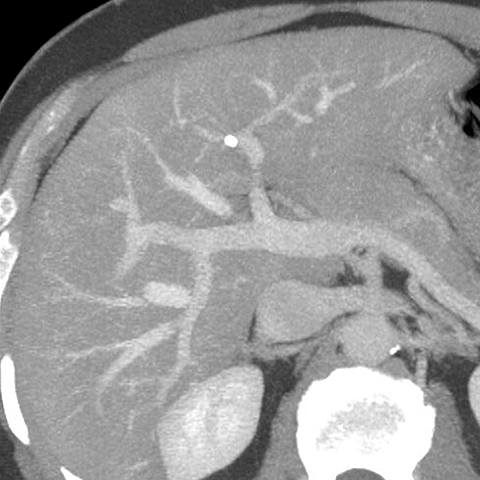

Normal Vessels, CT ( Axial ) [2 of 5]